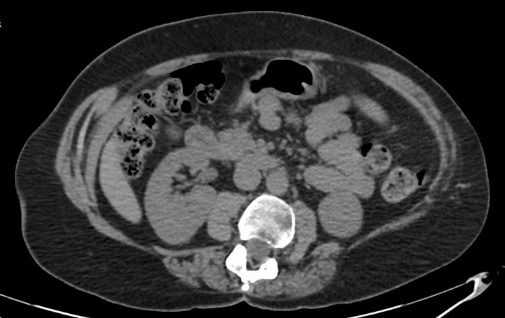

A 60-year-old female was assessed in pre op clinic for management of her symptomatic left lumbar incisional hernia. She presented with a lumbar bulge after surgery for scoliosis aged 17. The lumbar bulge could be reduced manually. Abdominal CT confirmed a left lumbar incisional hernia containing ascending colon, but no signs of obstruction or strangulation (Figure 1). During the consultation, a decision was made for an elective lumbar hernia repair. The patient provided consent for the anonymous publication of this case and accompanying images.

Figure 1: CT scan performed pre-operation (August 2016) showing left lumbar hernia.